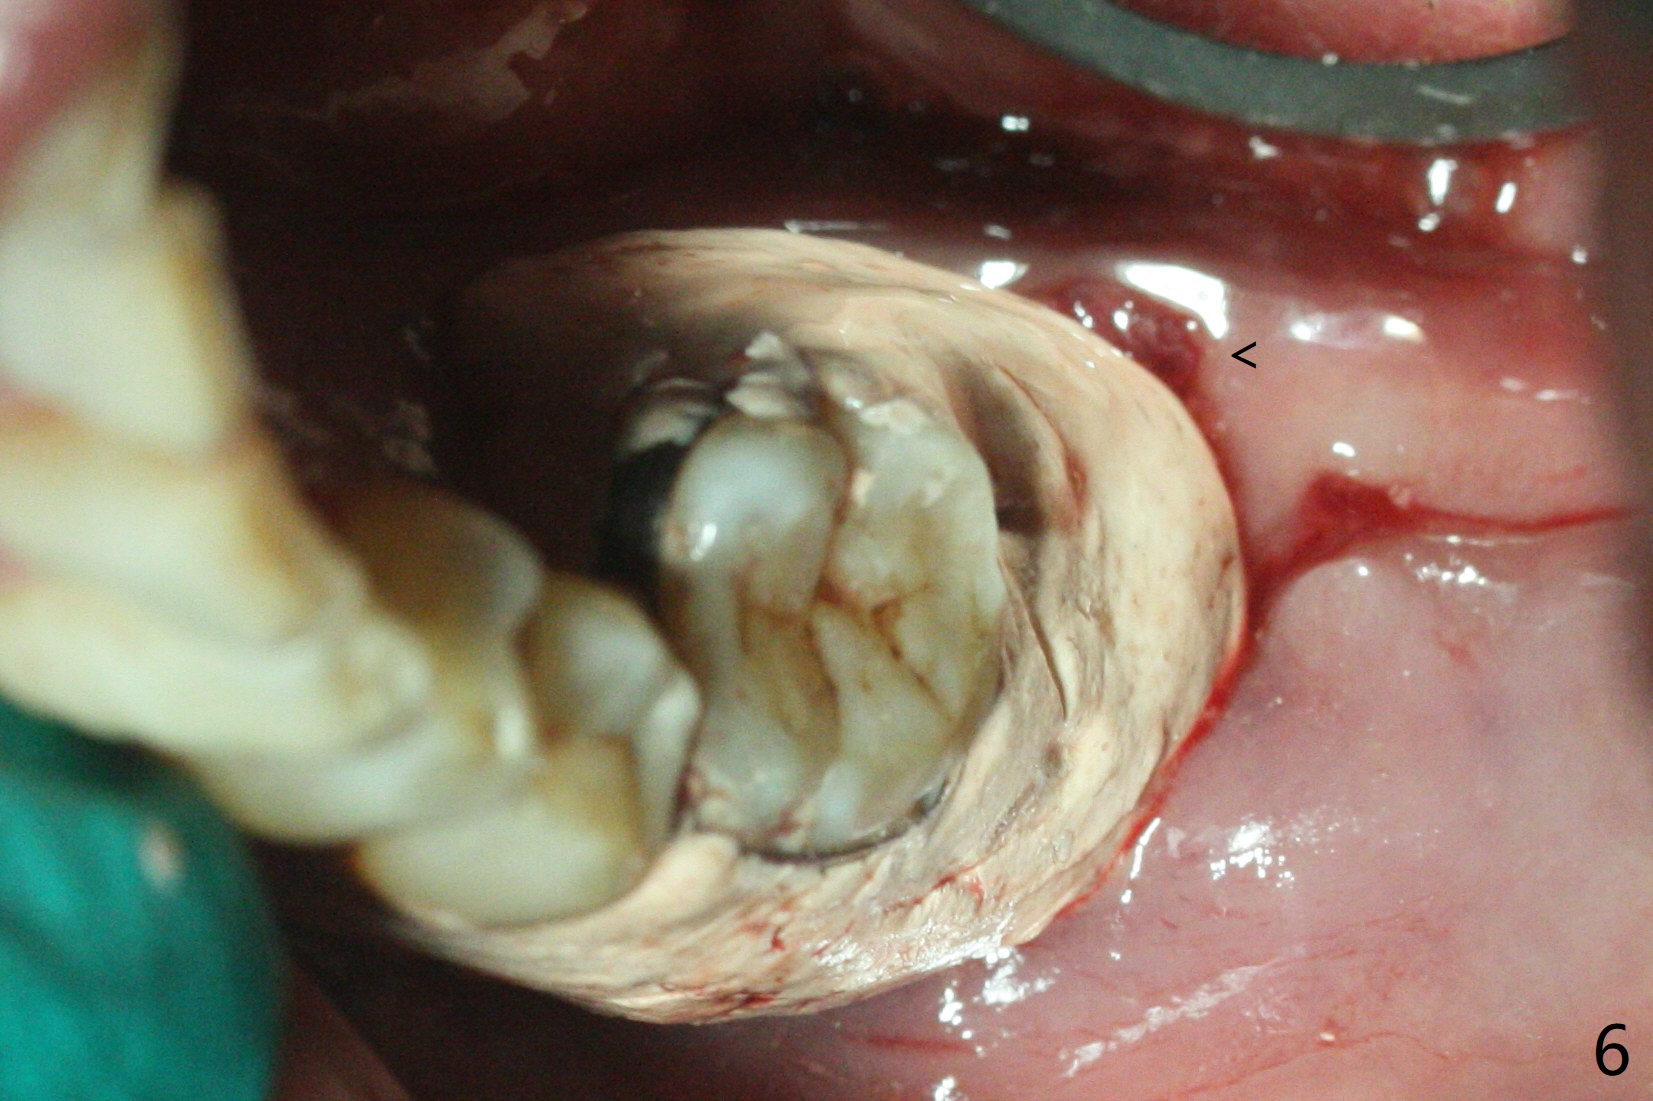

病人回来左下7拔牙植牙,十分感激导板取模后松动牙固位(图一),让他能正常吃饭。去除颊侧树脂和钢丝,6,7之间树脂自动脱落。拔牙后,肉芽组织很多,需要把局麻药注射至肉芽组织中,刮除时不慎远中舌侧牙龈穿孔。尽管纱布压迫,渗血相当多。怀疑导板就位不全,没有纠正。完成钻洞,报废植体无法就位。放置最后一个钻头,根尖片显示钻洞太浅了(图二)。再次磨除6颊侧,远中树脂,导板好像就位,重复钻洞,仍旧太浅(图三),CT表明钻洞偏颊侧(图四)。准备徒手改变钻洞,但是病人疼痛,只好植骨(粘性骨粉)(图五),牙槽窝舌侧,咬合面各覆盖一张PRF膜(图六:箭头),牙间隙维持器和牙周敷料固定。导板在曾经有树脂地方必须缓冲(图七:6;八:*,与图一对比),磨除深度有时不准确。术后两周牙周敷料仍稳定(图九),虽然病人希望撤除,我们偏向保留。反正病人正在做局部牙齿矫正。术后三周牙周敷料脱落,左上6咬合面树脂为了对侧局部牙齿矫正(图十)。骨粉有些丧失(图十一),最好手术时使用不可吸收膜。术后四个月牙槽窝充满骨粉,可以在下齿槽管颊侧植入4x8.5毫米植体(图十二)。